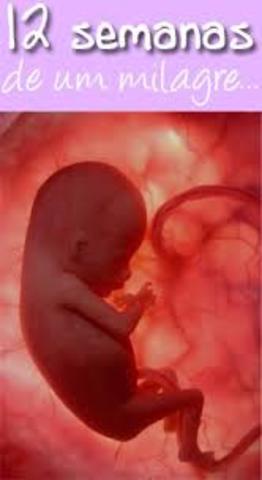

• (Feto 12 semanas):

(Feto 12 semanas):

En la semana 9 ., el peso del feto es de 8gr y al momento de nacer alcanza un peso aproximado de 3000gr

En el mismo lapso ., su longitud aumenta de 5cm a 50 cm ., en las semanas fetales la cabeza sigue siendo muy grande ., mientras que el tronco va aumentando poco a poco de tamaño